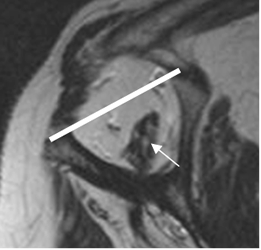

Fig 100. Ruptura del supraespinoso.

A: Rx AP. Cambios degenerativos con pérdida del espacio acromiohumeral y esclerosis asociada, por ruptura del supraespinoso.

B: TAC reconstrucción sagital y C: RM coronal en T1. Ruptura del supraespinoso, con pérdida del espacio acromiohumeral y lesiones osteocondrales.